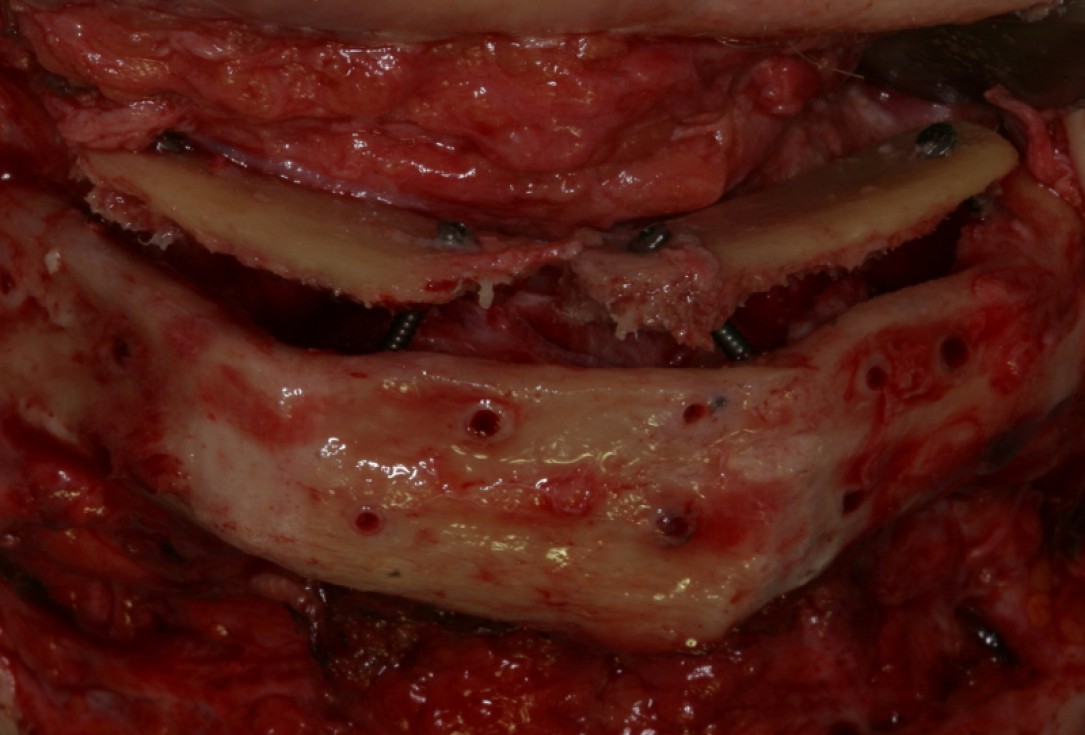

02/14 - Fixation of monocancellous bone splints from the iliac crest

Block augmentation with maxresorb®, collprotect® membrane & autologous bone blocks - Prof. Dr. Dr. D. Rothamel